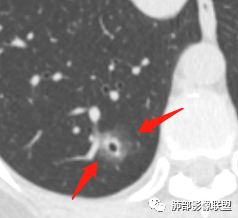

连续层面显示这个应该是空泡,或者小空洞,远端没有,近端也没有,周围环形软组织增厚。而空泡,影像上只是根据5mm界线,病理上不一定。

问一个问题,肺动脉肺静脉?为啥?

静脉,夹角90,周边没气管伴行。

静脉吧,动脉同时会伴有一根气管

这些呢?为啥?

动脉,有支气管伴行

伴有支气管

假如这是含气支气管,伴随的哪条动脉呢?近端从哪来?为啥环形壁增厚而又不均匀?都不太符合,所以支持空泡或小空洞。

上次刘纯老师提出,空泡征是一个影像征象,不是一个病理征象,我比较支持,他就是一个影像上的小低密度腔,原因很多,但是影像上与小的空洞表现区分不了。其中的原理:有一条是内容物排出后的残腔,其实也是空洞的原理。